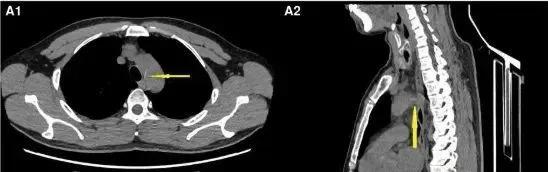

2023 年 4 月,患者因吃鱼误吞鱼刺,自行吞咽馒头后误以为鱼刺已脱落;2 天后,因胸骨后不适就诊当地医院,通过胸部 CT 意外发现鱼刺已穿透食管刺入胸主动脉,形成致命性食管主动脉瘘。

胸部断层 CT 影像:箭头所指白色条状物为鱼刺

当晚紧急开胸手术却未能找到鱼刺,术后复查显示鱼刺移位至腹腔动脉,遂转诊至华西医院。5 天后,在华西住院期间突发腹痛,经过多学科会诊最终锁定鱼刺已经游走至肝动脉,二次开腹手术后,才成功取出 2cm 鱼刺并修复血管。